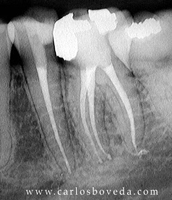

Video de un Retratamiento de Conductos en Una Sesión - (formato Quicktime)